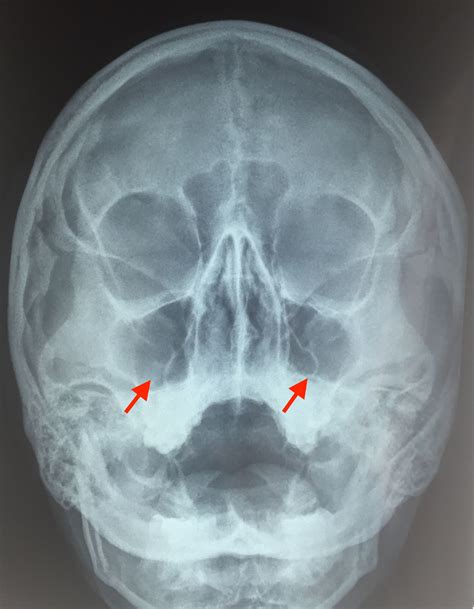

Как Выглядит Гайморит На Снимке Фото — Скачать ...

Симптомы гайморита